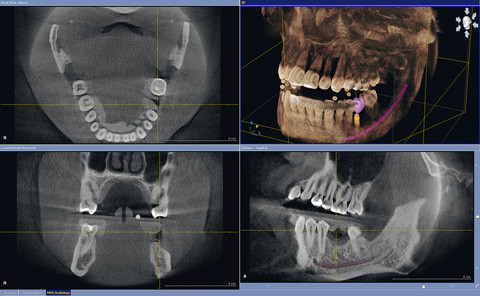

Abb.1 bis 3: Bildausschnitt eines DVT in Verbindung mit einer gängigen Software.

Abb. 2: Bildausschnitt eines DVT in Verbindung mit einer gängigen Software.

Abb. 3: Bildausschnitt eines DVT in Verbindung mit einer gängigen Software.

Jeder Hersteller bietet mit seinem Produkt eine Software zur Darstellung und Analyse der Daten an. Die Funktionen und anwählbaren Ansichten bestehen z.B. in der Auswahl von saggitaler, coronaler und axialer Ansicht, Transversalansichten und einer Panoramaübersicht. Die Daten werden zur Archivierung und Bearbeitung unter anderem im standardisierten Format DICOM (Digital Imaging and Communication in Medicine) gespeichert.